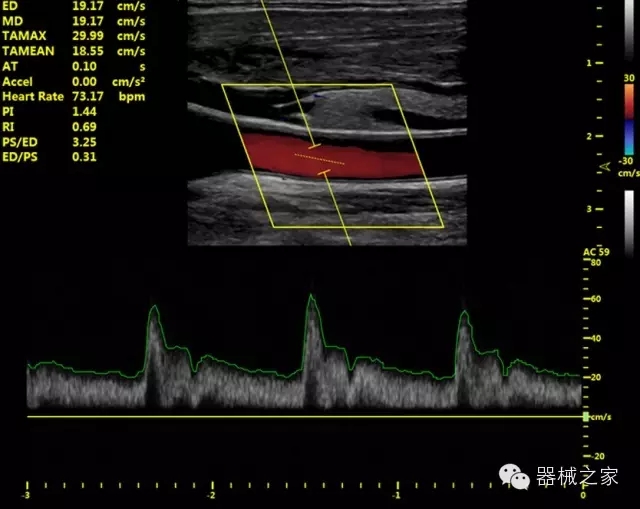

·獨(dú)有的HoloTM PW 實(shí)時(shí)3取樣門(mén)PW成像技術(shù),精確進(jìn)行血管診斷;

·一鍵優(yōu)化B、Color、PW,Auto Doppler自動(dòng)識(shí)別血管位置、偏轉(zhuǎn)角度等,提高工作效率;

·30°超廣角精細(xì)偏轉(zhuǎn)成像技術(shù),更優(yōu)異的頻譜圖像;

·IMT血管內(nèi)中膜自動(dòng)測(cè)量:為血管性疾病評(píng)估提供了有效的評(píng)估手段;